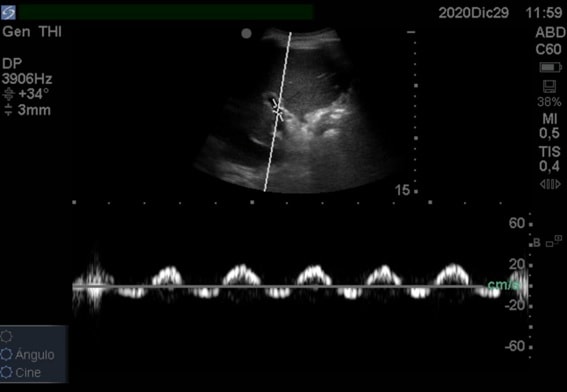

En esta imagen del hígado, puede verse la línea del Doppler, con su ROI en la mitad, en donde hay una línea con una cierta angulación que nos permite perfeccionar el ángulo de insonación para colocarnos perfectamente paralelos al flujo de la vena (en este caso, la vena porta). En la esquina superior izquierda de la pantalla se aprecia el ángulo corregido, en este caso +34º.

El Doppler pulsado es la representación gráfica de la velocidad y el sentido del flujo. Cuando activemos el modo Doppler pulsado en nuestro ecógrafo, aparecerá la línea de insonación (cuyo ángulo podremos modificar ligeramente mediante el comando “Steer”) y el ROI (la “caja” donde tomará la muestra el ecógrafo para representar el flujo).

Dentro de la pantalla aparecerán dos escalas y una línea de base. La escala vertical es la velocidad en cm/s habitualmente.